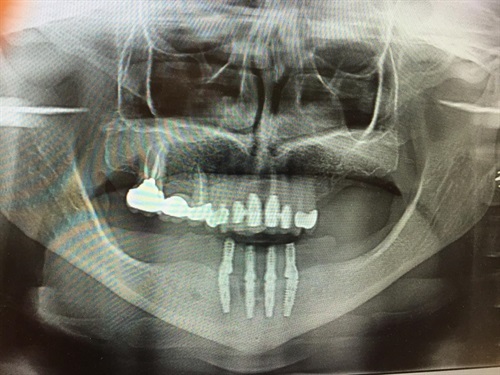

Image of a lower denture on 4 dental implants.Imagine you have lost all your upper teeth. You only have gums. The standard normal way to replace those teeth for you is with a full upper denture. AND, normally, that would be OK.

X-ray of the final implants in lower jawThey can also make up the temporary denture which will be fitted to the implants.

The tops of the 4 implantsHere's an animated video from Nobel Biocare illustrating how the principle of All On 4 implant surgery works;